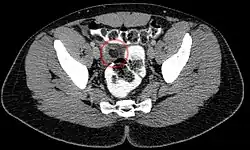

Diagnostic radiologique:

Le diagnostic est permis par la réalisation d'une tomodensitométrie. On retrouve au scanner une infiltration de la graisse épiploïque, de forme ovalaire formant une image dit en "navet" ou "signe de Hefny".